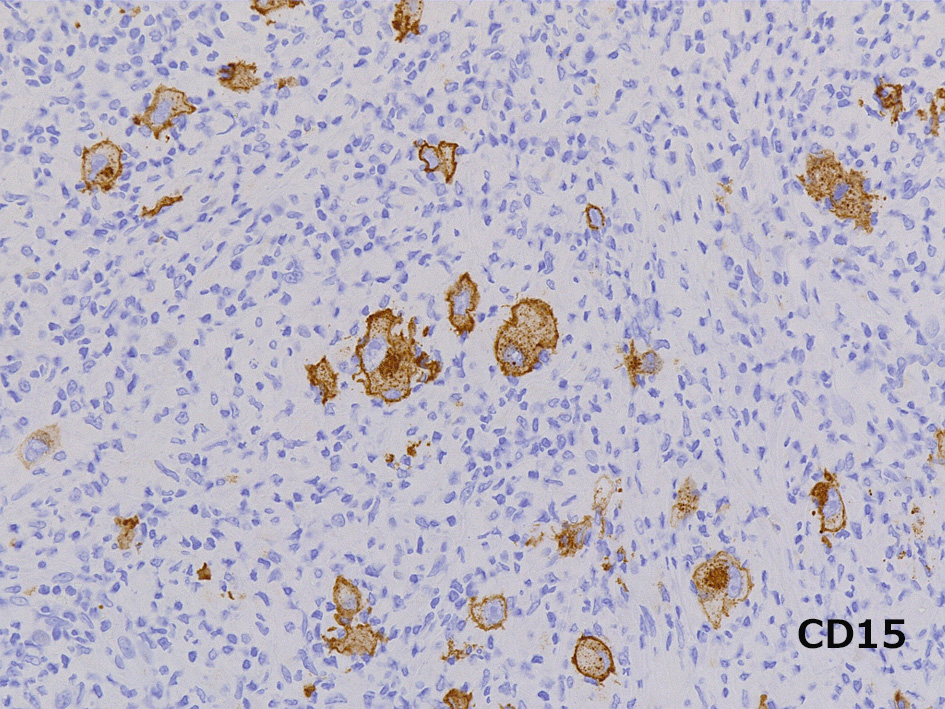

Hodgkin lymphoma-Case02-IWT

74歳男性 左頚部リンパ節腫大

組織球が類上皮細胞様に集蔟して肉芽腫様病変を形成, リンパ節内に明るく見えるエリアができている。HRS細胞が散在。背景はリンパ球, 形質細胞。好酸球が多く見られる

免疫染色

CD30, CD15は陽性, 転写因子のBob.1, OCT2は腫瘍細胞は陰性となる.